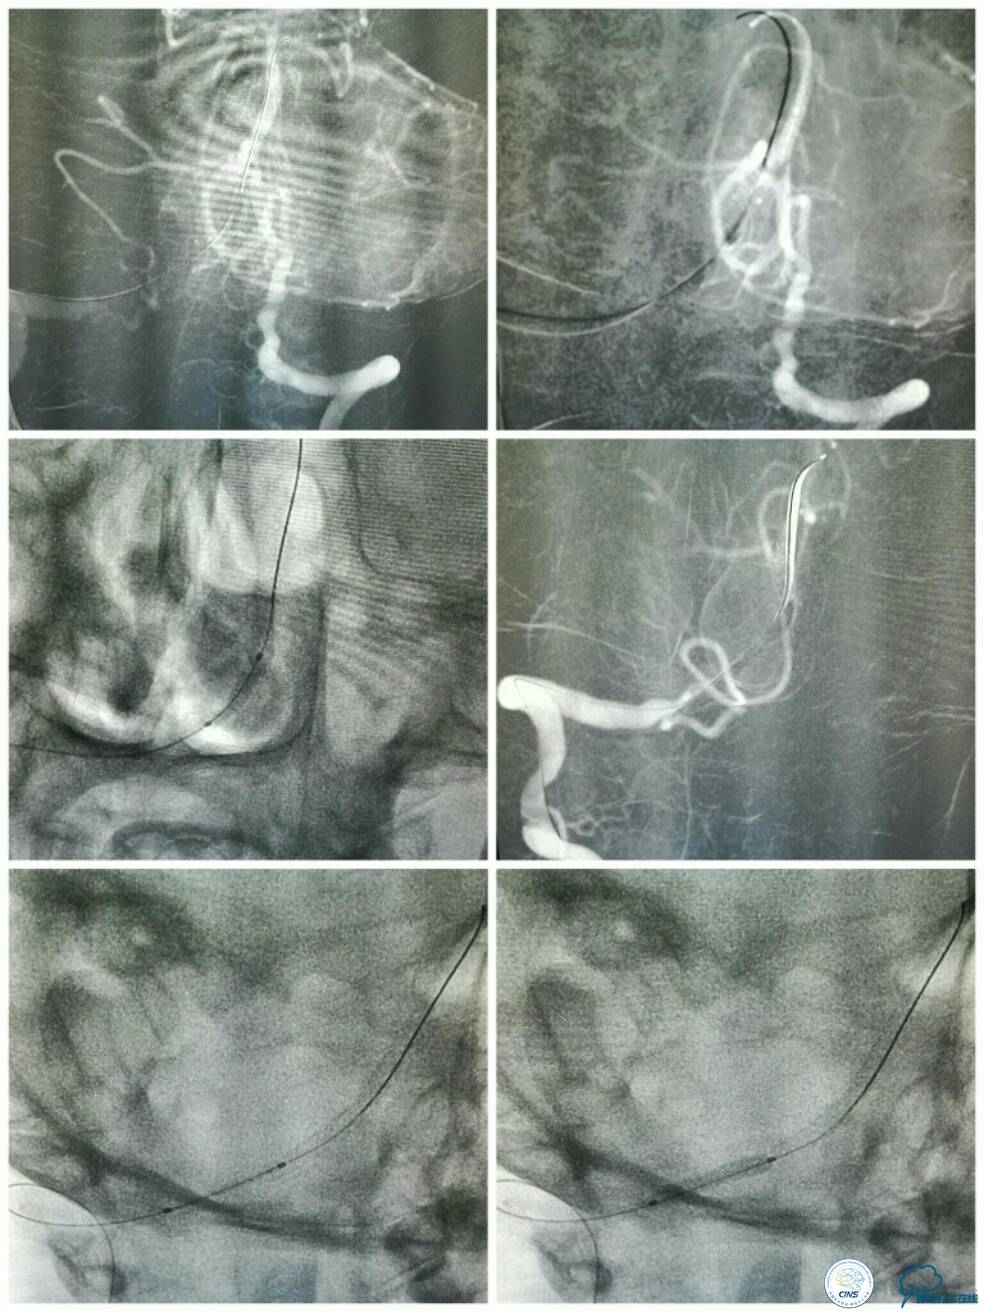

此时经6F导引导管和放置在左椎动脉V1段的5F椎动脉造影导管行双路径图,以显示椎基底动脉系统。选用Apollo球囊扩张支架(2.5 mm×13 mm 3枚,3.0×8 mm 1枚)自闭塞远端至近端依次释放支架,两个支架间重叠约2 mm(图10)。

图10